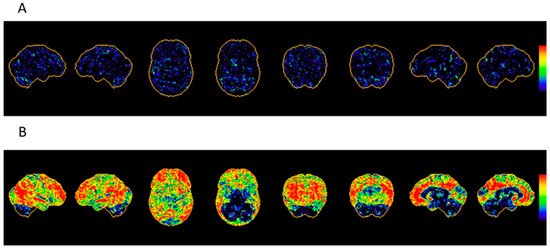

6.1.1. Imaging Data Display [45,50]

| Brain perfusion SPECT |

|

| FDG PET |